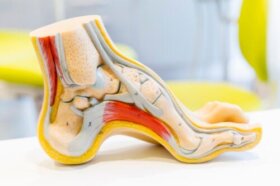

다리 통증은 전 세계적으로 의료 상담을 받는 일반적인 이유다. 운동 후는 물론 쉬고 있을 때도 다리가 아플 수 있다. 가만히…